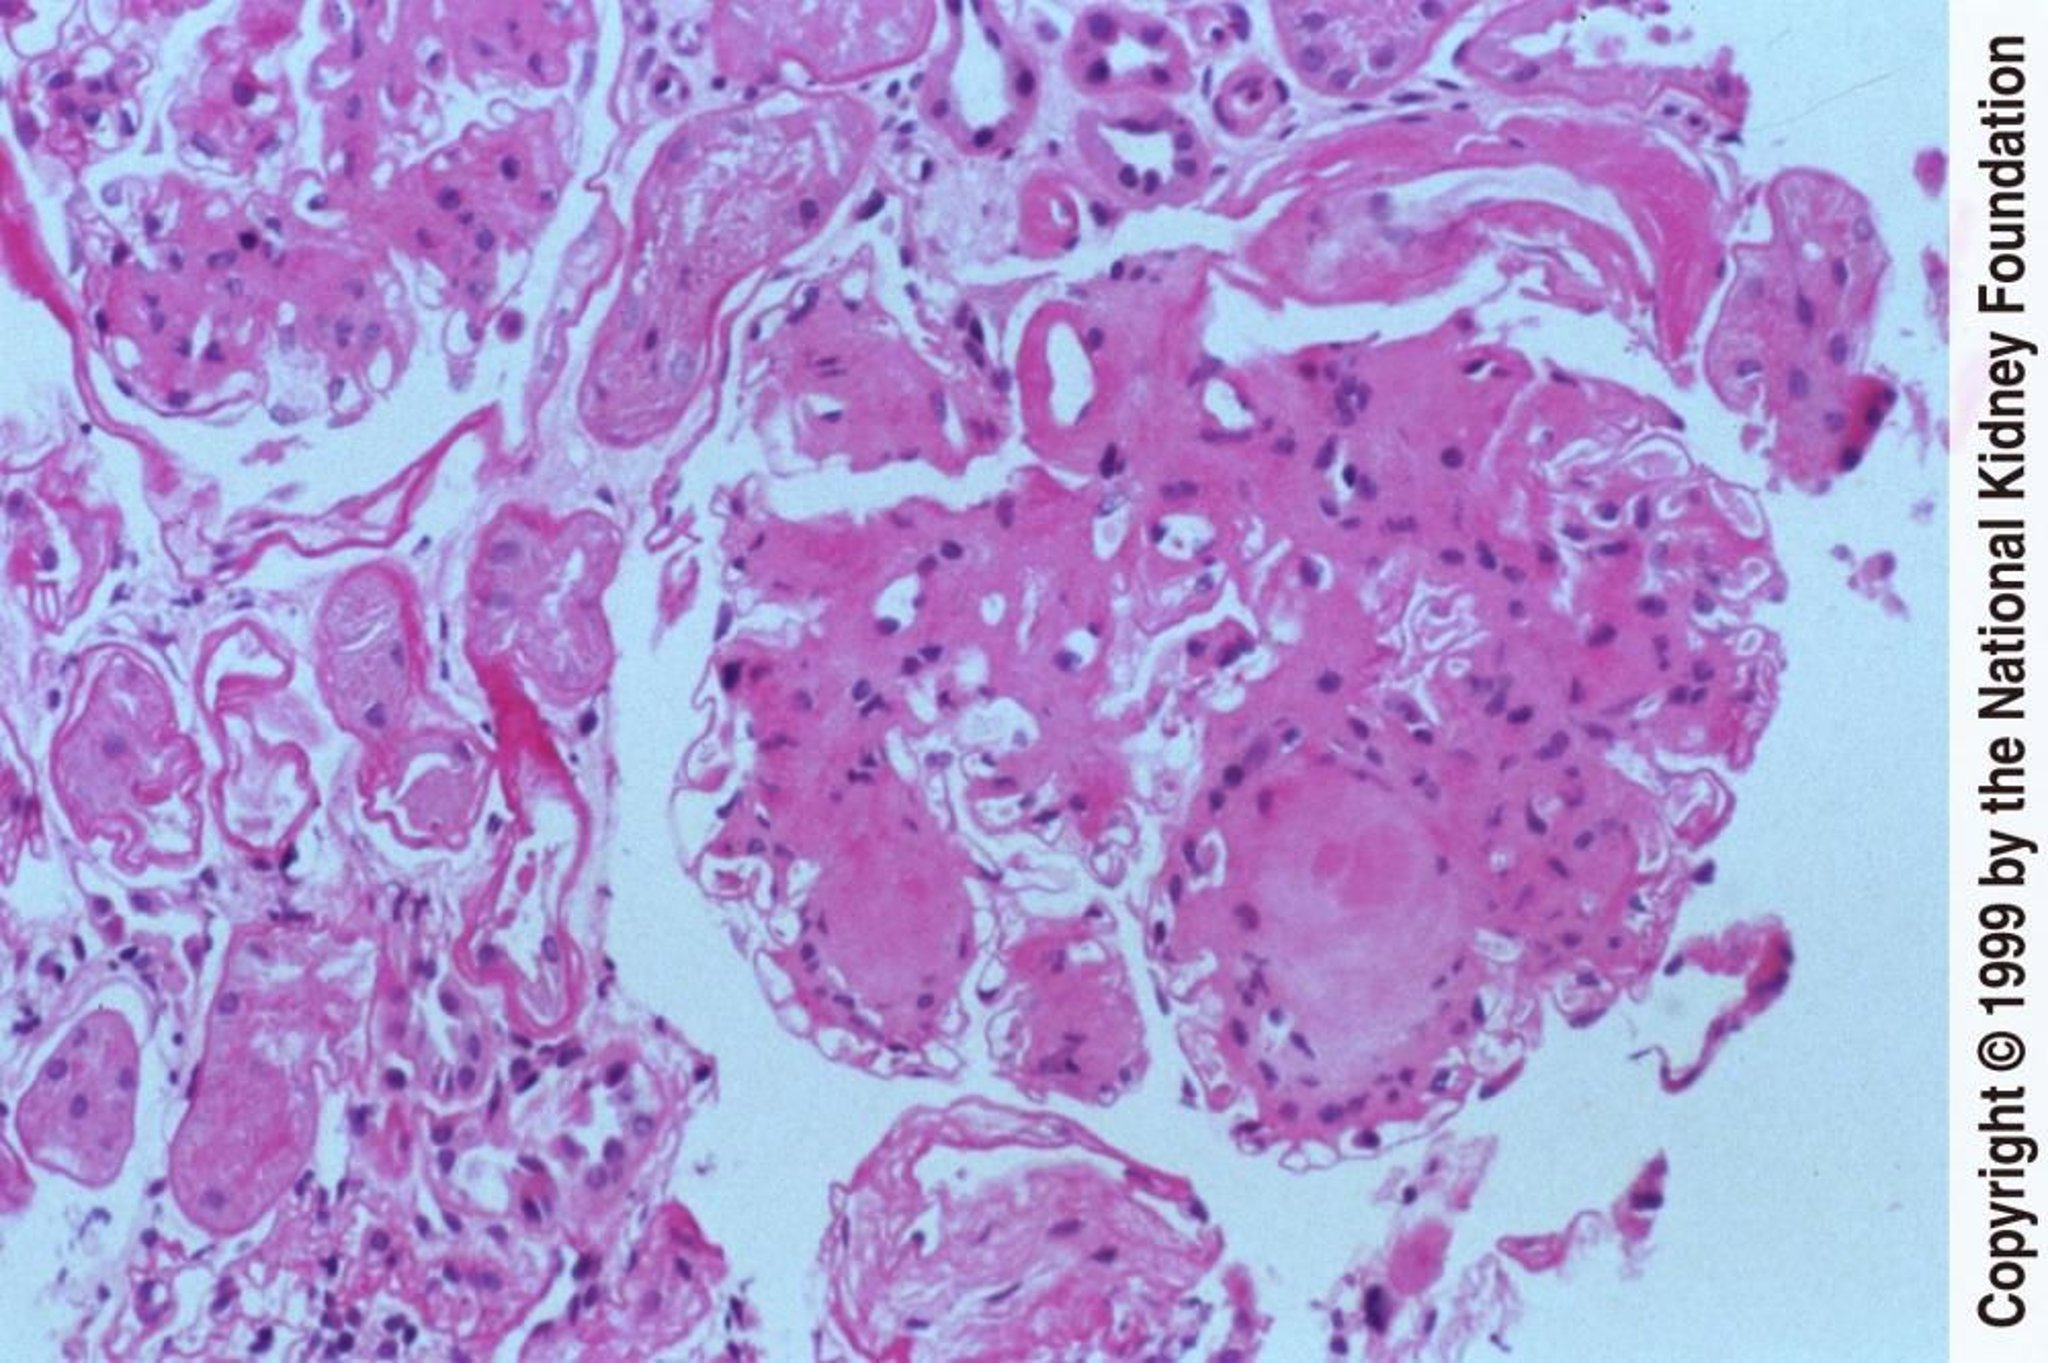

Діабетична нефропатія (вузлики)

Formation of acellular nodules within mesangial matrix is a distinctive feature of diabetic nephropathy (periodic acid-Schiff stain, ×200).

Image provided by Agnes Fogo, MD, and the American Journal of Kidney Diseases' Atlas of Renal Pathology (see www.ajkd.org).